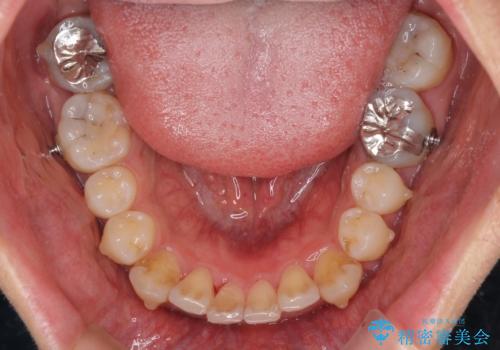

- 口元の突出感を治したいとのことで来院された患者様です。

上下顎ともにIPR(歯と歯の間を削る)と歯列全体の拡大によって口元が引っ込むように設計し、インビザラインにより治療を行うこととしました。

抜歯をして口元を下げなければならないほど出っ歯ではなかったため、少しずつ治療ゴールを変更しながら仕上げていきました。

気になっていた前歯の飛び出した印象は、最終的にはスッキリと引っ込み、大変満足していただきました。